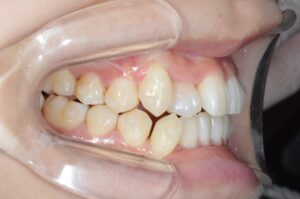

①写真撮影

今の歯並びを色々な角度から撮影します。

せっかくなので矯正前→現在(No.40)で並べてみます。

ぎゅうぎゅうに詰まっていたのが少し緩和されています。